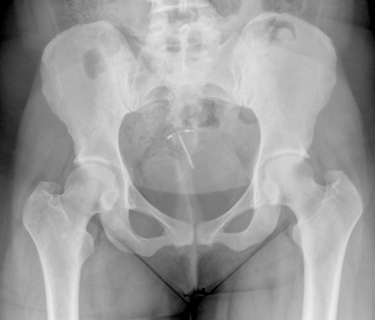

Allegedly, the Mirena IUD can cause a number of complications to women who are implanted with the Bayer contraceptive device, including uterine perforation and migration. This means that Mirena can allegedly punch through the uterine wall and move around inside the body, damaging the uterus and other abdominal and pelvic organs. Allegedly, this can promote other Mirena complications like infection, permanent sterility, and miscarriage.